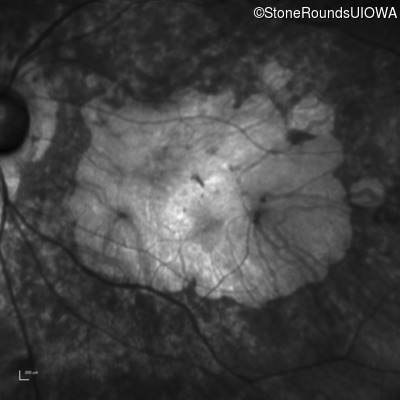

Infrared Fundus Photograph - Right - 10/200 sc

Exemplar